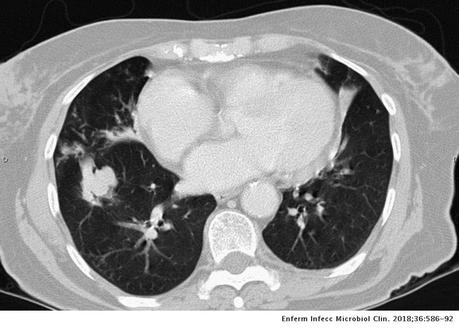

Vía aérea y pulmones: Con ventana para pulmón se observa hacia el segmento superior del lóbulo inferior derecho la presencia de una lesión cavitada, la cual tiene un diámetro máximo de 3.3 cm, además ambos pulmones presentan algunas áreas con patron micronodular, predominantemente hacia lóbulos medio y língula. La tráquea se aprecia central, sin alteraciones.

- ESTUDIO TOMOGRÁFICO DE TORAX QUE MUESTRA HALLAZGOS QUE PUDIERAN CORRESPONDER CON PROCESO INFECCIOSO DE TIPO GRANULOMATOSO NO TUBECULOSO (MICOBACTERIUM AVIUM) COMO PRIMERA POSIBILIDAD, SIN EMBARGO, LA POSIBILIDAD DE QUE PROCESO TUBERCULOSO O FIMICO NO PUEDE SER DESCARTADO.